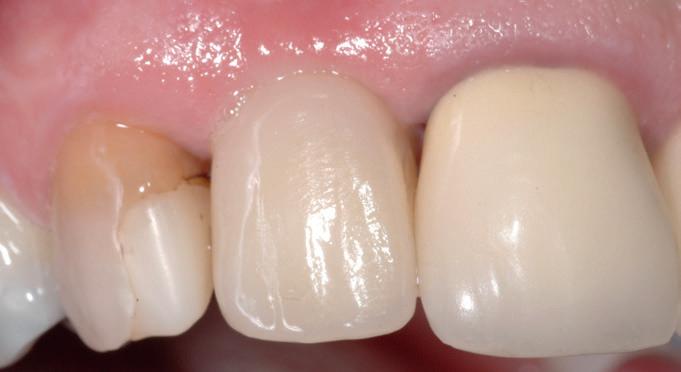

Toekomstige AI-ondersteunde software zal vermoedelijk nog beter risico’s voorspellen op basis van slijtagepatronen, speekselanalyse en leefstijlfactoren. Echter, wanneer er geen scanner in de praktijk beschikbaar is dan is een handige tool het vragen of iemand elke periodieke afspraak zijn retainer meeneemt ter controle. Ontstaan daar slijtfacetten in dan weet je dat iemand s nachts actief is en zul je over moeten gaan op een night guard zoals in het voorbeeld van afbeelding 7-10). Wanneer verwijs je door?

In alle bovengenoemde gevallen is het goed om te overleggen met de tandarts wanneer hij wenst in te grijpen bijvoorbeeld zoals zichtbaar op afbeelding 13 en 14. Wanneer er nog sprake is van cuspidaatgeleiding kan je besluiten om dit te monitoren en splint therapie te adviseren. Maar wanneer cuspidaatgeleiding verdwijnt en overgaat in groepsgeleiding zal de tandarts de cuspidaat kunnen opbouwen en vervolgens een splint aanmeten. Dit zijn zaken die een mondhygiënist ook kan herkennen. Evenals afbeelding 14 waar sprake is van een constricted envelope of function. Dit houdt in dat iemand zichzelf op slot zet, waardoor vaak sneller slijtage ontstaat palatinaal van het bovenfront en buccaal van het onderfront. Dit verdient aandacht en dient, nog voordat de eerste tekenen van slijtage optreden, een red flag te zijn en besproken te worden met de tandarts en de patiënt.